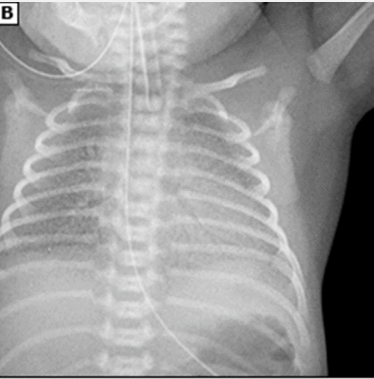

preterm, low, ground glass

RDS: Diagnosis

-________ infant with progressive respiratory distress/failure shortly after birth

-CXR shows ___ lung volume, diffuse ______ _______ appearance with air bronchograms. This is a result of alveolar atelectasis contrasting with aerated airways